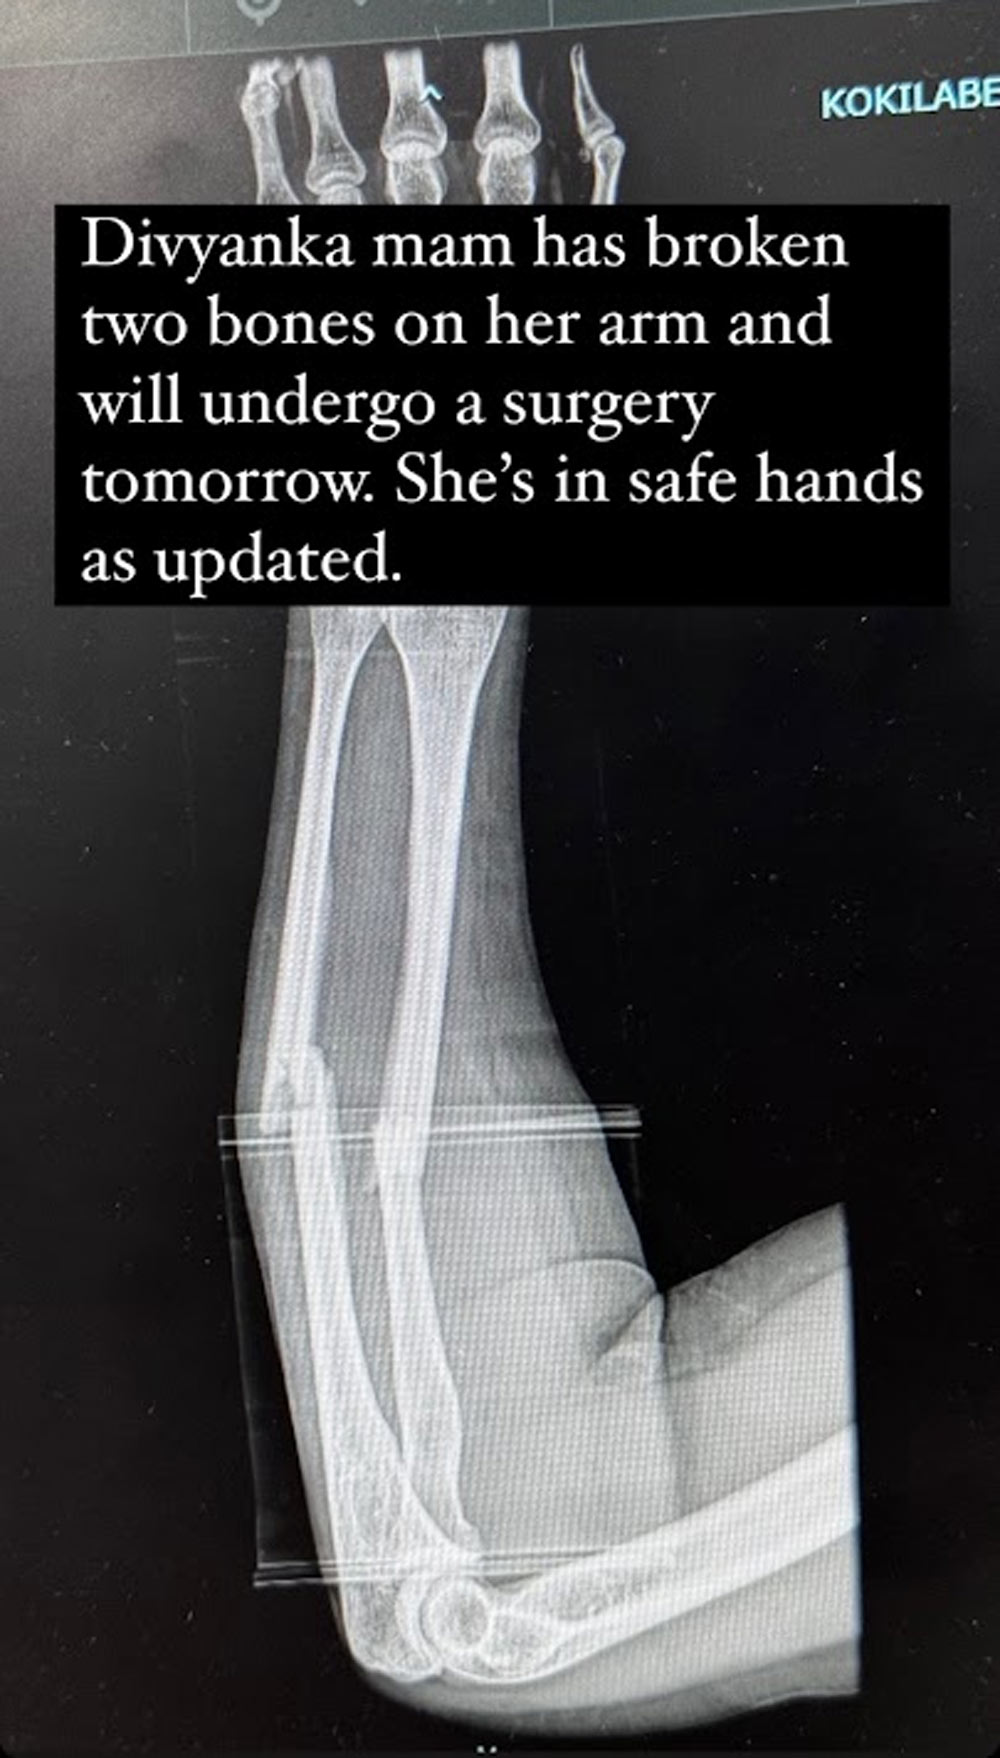

Vivek Dahiya, alongside Divyanka's publicist, took to social media to inform fans about Divyanka’s injury and upcoming surgery. Expressing regret over the postponement of his live session, Vivek requested support and understanding from their followers. He assured everyone that Divyanka was receiving the best medical attention and asked for prayers for her speedy recovery.

A thorough examination by a medical professional is crucial for diagnosing a forearm fracture. This may involve physical assessments, checking for signs of injury, and ordering X-rays to confirm the diagnosis and assess the extent of the fracture. Prompt diagnosis and treatment are essential to prevent further complications and promote optimal healing.